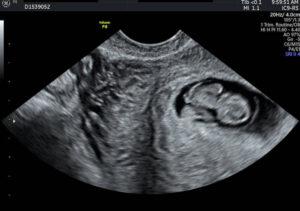

This is the post that I never imagined having to write when I found out I was pregnant. I lost my baby at…